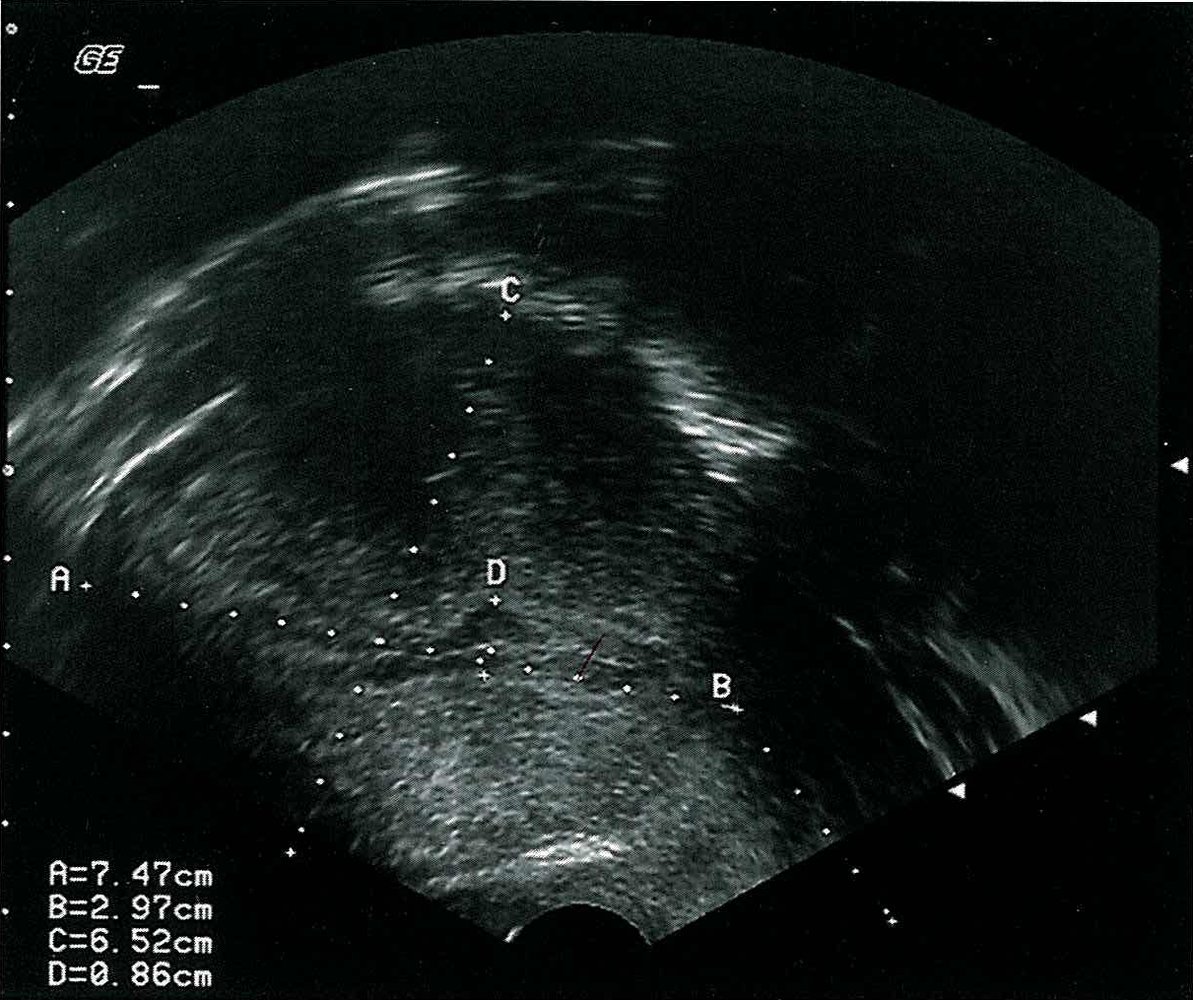

Breast ultrasound

Breast ultrasound can be used to assess breast lesions which were detected by palpation, mammography, and/or breastMRI scans. Ultrasound can also be used to assess the axilla for lymph node involvement if there is suspicion for breast cancer.

References:[15]